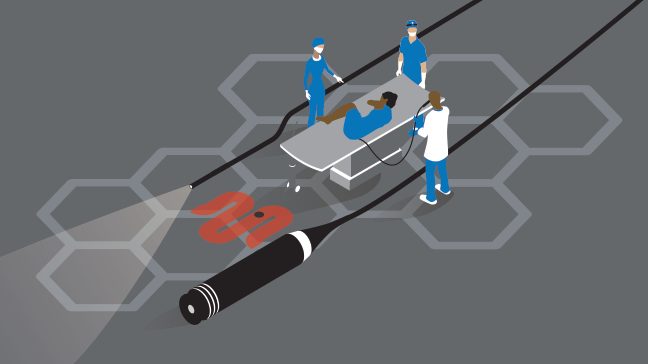

You may see blood in your semen after a medical procedure, such as a vasectomy, prostate biopsy or cystoscopy.

- Cystoscopy: Your doctor will use a scope to look inside your bladder and urethra.